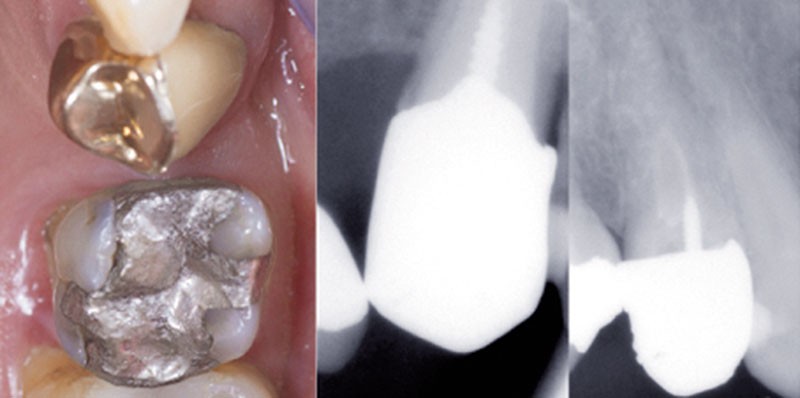

Parmi ces indications, le retraitement endodontique constitue l’une des plus fréquentes. En effet, une étude réalisée sur une période de 3 ans, sur 2000 patients, [3] estime qu’en moyenne, le retraitement endodontique orthograde représente un peu moins de 40 % de tous les actes effectués en endodontie. Et parmi ces dents retraitées, 25 % sont restaurées par une prothèse. Ce qui concerne potentiellement 10 % de toutes les interventions en endodontie.

Accéder aux anciennes obturations endodontiques de manière efficace nécessite donc de déposer intégralement les couronnes et les éventuelles reconstitutions coronoradiculaires sus-jacentes. En effet, réaliser une cavité d’accès à travers une couronne prothétique qui ne reproduit pas forcément les volumes de la dent initiale, peut induire un risque de perforation camérale et constituer un échec immédiat du traitement [4]. De plus, un…